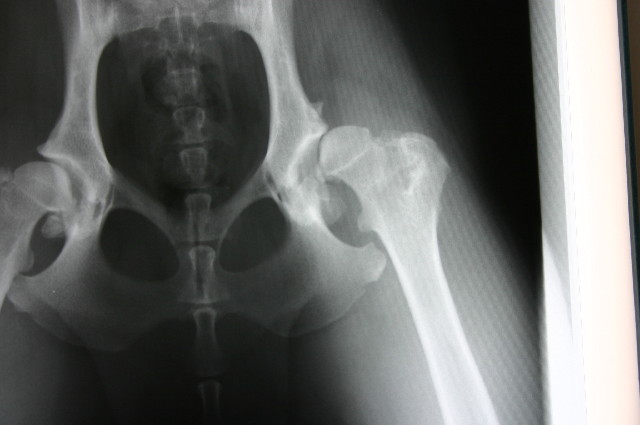

今日はもいちゃんが【肛門嚢切除手術】をして術後1日目。